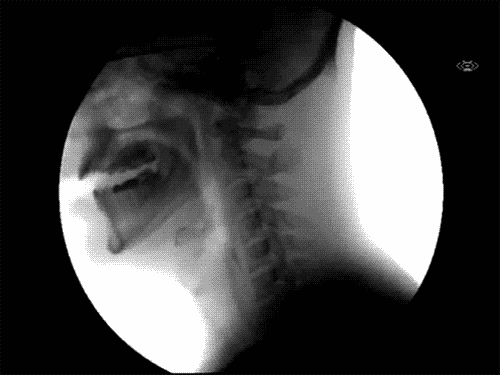

kako to izgleda kada gutamo